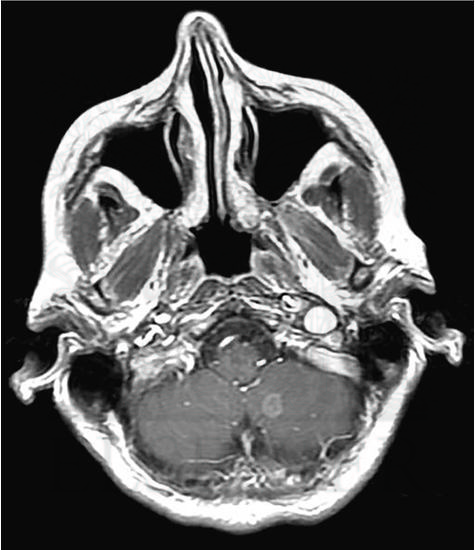

Axial, Gadolinium Contrast–Enhanced T1-Weighted Magnetic Resonance Image Shows 6-mm Enhancing Metastasis in Left Cerebellar Hemisphere